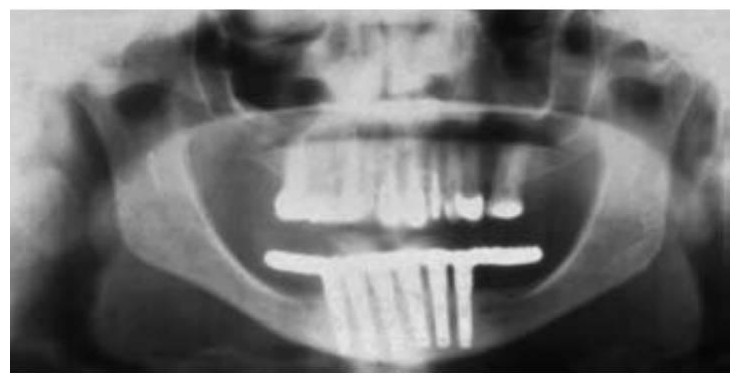

Un espacio de altura coronaria superior a los 15 mm es excesivo; principalmente es consecuencia de la pérdida vertical de hueso por un edentulismo de larga duración. Otras causas pueden ser la genética, un traumatismo o el fracaso de los implantes (cuadro 6-4). El tratamiento del excesivo EAO antes de la colocación de los implantes incluye procedimientos ortodóncicos y quirúrgicos. La ortodoncia es el método de elección en pacientes parcialmente edéntulos, ya que otros tratamientos quirúrgicos o protésicos son más costosos y presentan un riesgo mayor de complicaciones. También se deberían considerar ciertas técnicas quirúrgicas, incluyendo injertos onlay óseos en bloque, injertos de hueso particulado con mallas de titanio o membranas de barrera, injertos óseos interposicionales o la osteogénesis por distracción. A menudo se prefiere realizar una única cirugía para la reconstrucción de los maxilares y la colocación de los implantes, especialmente cuando se quiere ganar en volumen óseo. Cuando se necesita aumentar significativamente la altura vertical ósea se precisan múltiples procedimientos quirúrgicos.

La osteogénesis por distracción presenta varias ventajas para el crecimiento vertical del hueso, respecto de las técnicas de injerto óseo onlay. La ganancia de hueso vertical no se ve limitada por factores como el tamaño del injerto o la expansión del volumen del tejido blando existente. No existe morbilidad del área donante y se puede realizar la cirugía en el gabinete dental. Sin embargo, la distracción ósea requiere de la colaboración del paciente y el aumento de volumen óseo es unidireccional. Además, los estudios clínicos han encontrado que, a menudo, se necesitan posteriores procedimientos de aumento de hueso para la colocación de los implantes dentales70. Misch presentó una técnica única en la que combinaba la distracción ósea vertical con injertos de hueso onlay horizontales para la reconstrucción tridimensional del defecto. Primero se realiza la distracción ósea para aumentar la cresta verticalmente y expandir el volumen del tejido blando. Seguidamente, se usa un injerto óseo onlay para terminar de repara el defecto (fig. 6-29).